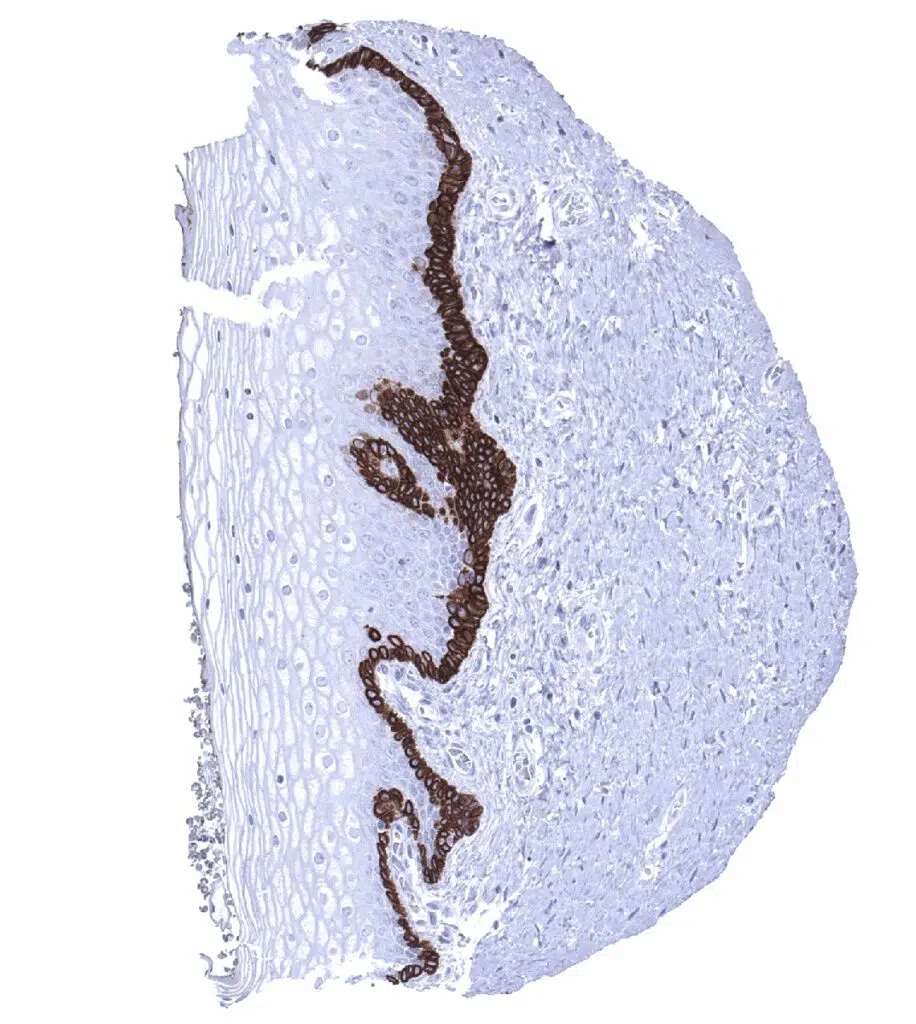

Esophagus, squamous epithelium - Cytokeratin 19 staining is usually limited to the basal cells. In this sample some additional "higher" Cytokeratin 19 positive squamous cells are seen.